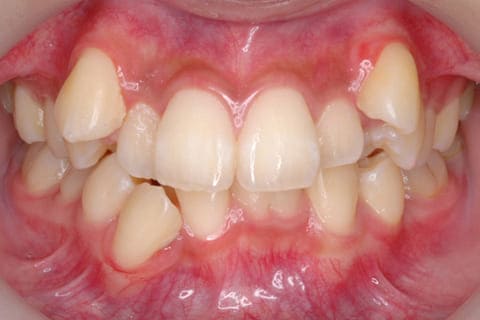

歯並びが気になる

Dentition

凸凹・乱ぐい歯・出っ歯・すきっ歯などの歯並びに関する症状でお悩みの方へ

健康に美しく臨床実績集

虫歯や歯周病、事故などでの欠損、

噛めるようになりたい、見た目の美しさの追求など、

審美的に機能的に回復した治療経過報告症例です。